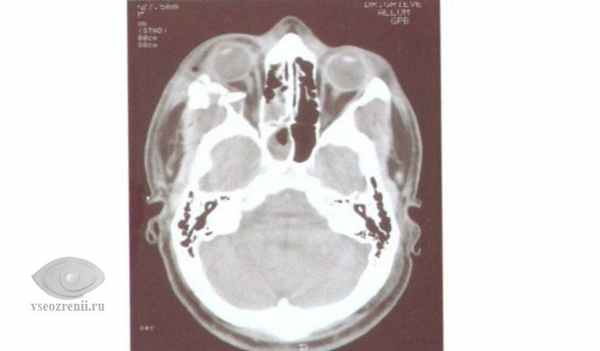

Нами не отмечено осложнений после использования трансконъюнктивального доступа с латеральной кантотомией, а именно лимфостаз нижнего века, отставание нижнего века от глазного яблока и слезотечение [2]. Вышеперечисленные осложнения отмечались при субцилиарном доступе. У 2 (3,63%) пациентов сохранялся хемоз в течение 2—3 нед, что было обусловлено длительностью операции, в связи с наличием обширного повреждения нижней стенки орбиты и хронического полипозного верхнечелюстного синусита (рис. 1—3).

Рис. 2. Пациент В. КТ (сагиттальный срез). Перелом нижней стенки правой орбиты, хронический верхнечелюстной синусит (до операции). Рис. 3. Пациент В. КТ (сагиттальный срез). Состояние после реконструкции нижней стенки правой орбиты титановой мини-пластиной и санации верхнечелюстного синуса. Рис. 1. Пациент В. Сохраняется выраженный хемоз после реконструкции нижней стенки правой глазницы (10-е сутки).